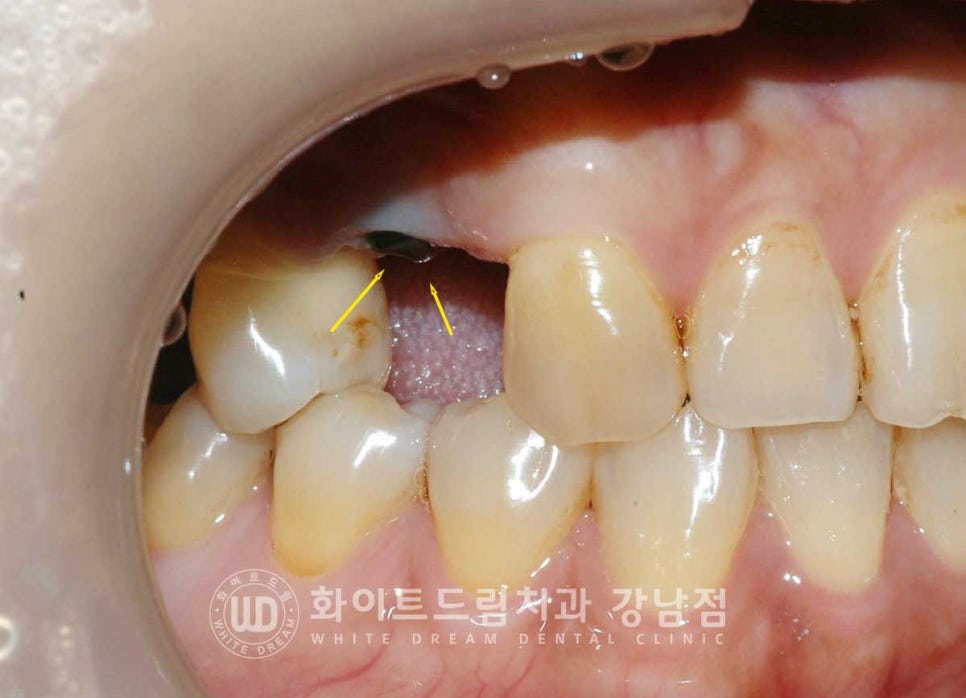

▲ 46번 인레이가 떨어진 치아 부위, 신경이 겉으로 노출되어 있는 상태여서 신경치료를

진행하게 되었습니다.

이렇게 뿌리만 남은 치아들은

턱뼈까지 연결되어 있는 신경관이 겉으로 노출되어 있기에

잇몸뼈 내부 염증이 쉽게 발생하게 됩니다.